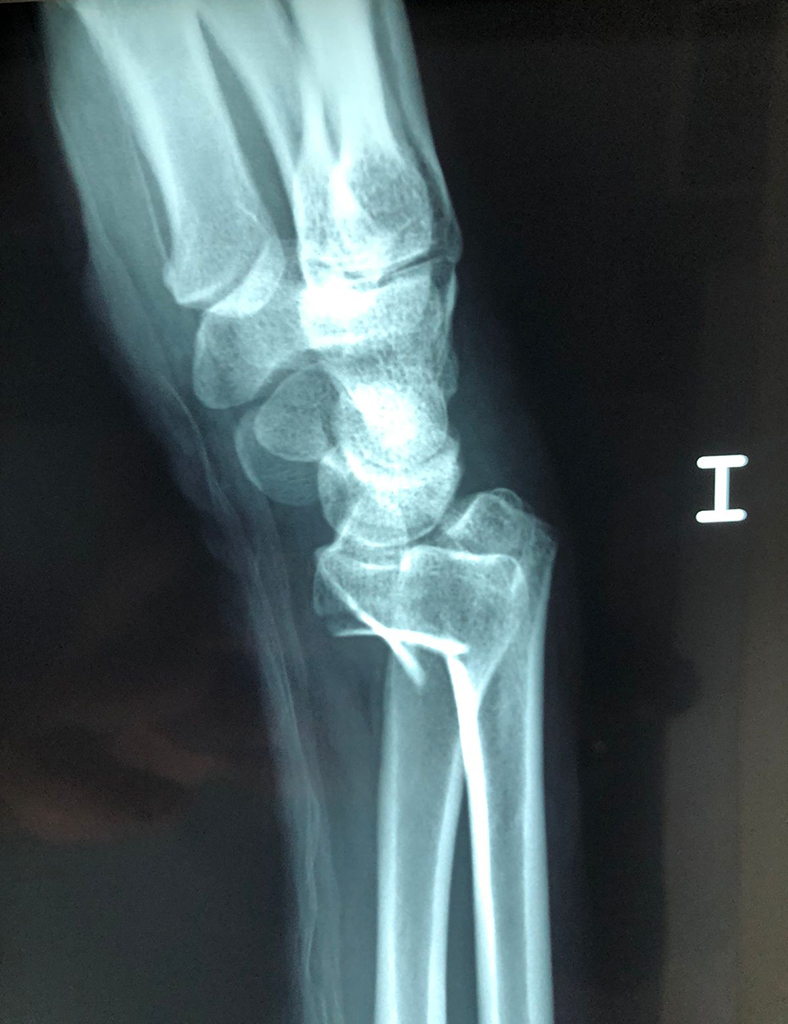

Calcaneo - Cirugías de Muñecas y Manos

Los procedimientos más comunes en cirugía de la mano son aquellos destinados a reparar traumatismos, incluyendo lesiones de tendones, nervios, vasos sanguíneos, y articulaciones; huesos fracturados; y quemaduras, cortes, y otros daños de la piel.